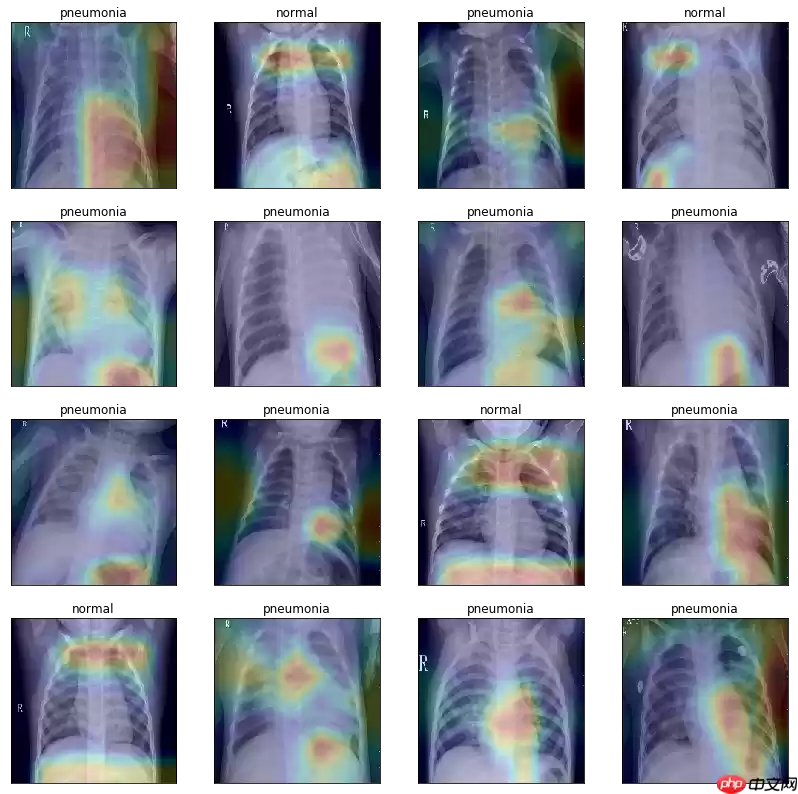

绘制类激活图,可视化模型效果

In [86]# 获取 Grad-CAM 类激活热图def get_gradcam(model, data, label, class_dim=2): conv = model.conv_layer(data) # 得到模型最后一个卷积层的特征图 predict = model.last_layer(conv) # 得到前向计算的结果 label = paddle.reshape(label, [-1]) predict_one_hot = paddle.nn.functional.one_hot(label, class_dim) * predict # 将模型输出转化为one-hot向量 score = paddle.mean(predict_one_hot) # 得到预测结果中概率最高的那个分类的值 score.backward() # 反向传播计算梯度 grad_map = conv.grad # 得到目标类别的loss对最后一个卷积层输出的特征图的梯度 grad = paddle.mean(paddle.to_tensor(grad_map), (2, 3), keepdim=True) # 对特征图的梯度进行GAP(全局平局池化) gradcam = paddle.sum(grad * conv, axis=1) # 将最后一个卷积层输出的特征图乘上从梯度求得权重进行各个通道的加和 gradcam = paddle.maximum(gradcam, paddle.to_tensor(0.)) # 进行ReLU操作,小于0的值设为0 for j in range(gradcam.shape[0]): gradcam[j] = gradcam[j] / paddle.max(gradcam[j]) # 分别归一化至[0, 1] return gradcam# 将 Grad-CAM 叠加在原图片上显示激活热图的效果def show_gradcam(model, data, label, class_dim=2, pic_size=224): gradcams = get_gradcam(model, data, label,class_dim=class_dim) for i in range(data.shape[0]): img = (data[i].numpy() *127.5 +127.5).astype('uint8').transpose([1, 2, 0]) # 归一化至[0,255]区间,形状:[h,w,c] heatmap = cv2.resize(gradcams[i].numpy() * 255., (data.shape[2], data.shape[3])).astype('uint8') # 调整热图尺寸与图片一致、归一化 heatmap = cv2.applyColorMap(heatmap, cv2.COLORMAP_JET) # 将热图转化为“伪彩热图”显示模式 superimposed_img = cv2.addWeighted(heatmap, .2, img, .8, 1.) # 将特图叠加到原图片上 return superimposed_imgmodel_path = 'checkpoint/final.pdparams'model = ResNet( class_dim=2)para_state_dict = paddle.load(model_path)model.set_dict(para_state_dict)model.eval()test_txt = 'work/data/test_list.txt'test_dataset = XChestDateset(test_txt,val_transform, 'test')test_loader = DataLoader(test_dataset, shuffle=True, batch_size=16 )dataiter = iter(test_loader)images, labels = dataiter.next()num = images.shape[0]row = 4fig = plt.figure(figsize=(14,14))for idx in range(num): ax = fig.add_subplot(row,int(num/row), idx+1, xticks=[], yticks=[]) image = paddle.unsqueeze(images[idx], axis=0) heat_map = show_gradcam(model, image, labels[idx], class_dim=2) heat_map = cv2.cvtColor(heat_map, cv2.COLOR_BGR2RGB) plt.imshow(heat_map) if labels[idx]: ax.set_title('pneumonia') else: ax.set_title('normal')登录后复制/opt/conda/envs/python35-paddle120-env/lib/python3.7/site-packages/paddle/fluid/dygraph/varbase_patch_methods.py:373: UserWarning: Warning:tensor.grad will return the tensor value of the gradient. warnings.warn(warning_msg)登录后复制